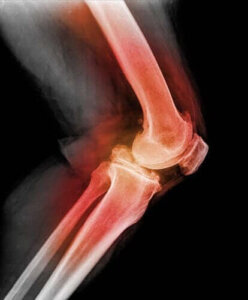

För att diagnostisera en dislokation av en knäskål eller en patelladislokation kommer läkaren att röra vid knäskålen och böja knäet och flytta det i olika riktningar. Genom att använda röntgen, magnetresonanstomografi (MRI), eller datortomografi (CT), kan läkaren se bilder av knäskålen och andra eventuella skador i området.